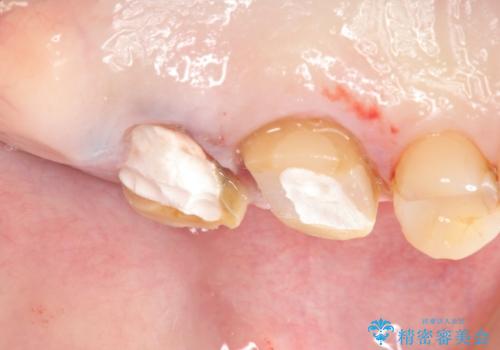

- 半年前から奥歯から嫌な臭いがする、と治療を求めて来院されました。

銀歯を除去したところ、虫歯が大きく再発しこのままではかぶせ直しができないような状況でした。